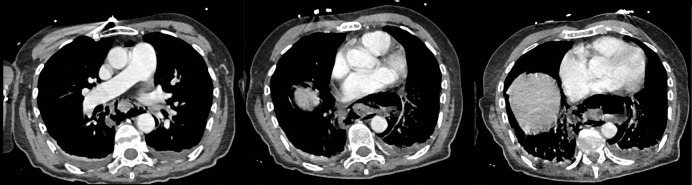

本文报告一位70岁女性患者,长期以进食困难伴固体食物为主诉,报告Boerhaave综合征。她腹痛24小时,伴有恶心和粪便性呕吐。患者有呼吸急促、心动过速、缺氧、腹部守卫、无肠音。胸腹计算机断层扫描显示幽门壁明显增厚,伴有继发性胃膨胀、颈部皮下肺气肿、双侧胸腔积液和纵隔气肿。

A case is presented of Boerhaave syndrome in a 70‑year‑old female patient complaining of dysphagia with solids for a long time. She consulted for abdominal pain for 24 hours, accompanied by nausea and fecal vomiting. The patient had tachypnea, tachycardia, hypoxia, abdominal guarding, and absence of bowel sounds. Thoracoabdominal computed tomography revealed significant pyloric wall thickening with secondary gastric distension, cervical subcutaneous emphysema, bilateral pleural effusion, and pneumomediastinum.